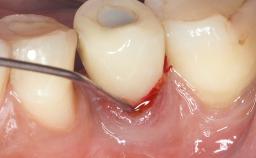

Surgical Management of Peri-Implantitis: Removal of Implant Due to Recurrent Infection Using an Implant-Retrieval Tool

Despite anti-infective surgical treatment, some patients may experience recurrent infection and progressive bone loss requiring additional treatment. This case describes a conservative approach using an implant retrieval tool without the need for excessive bone removal or use of a trephine.

A 65-year-old female patient was referred to the periodontist for assessment and management of infection associated with an implant at site 12. The general dentist had noted suppuration on probing during examination.